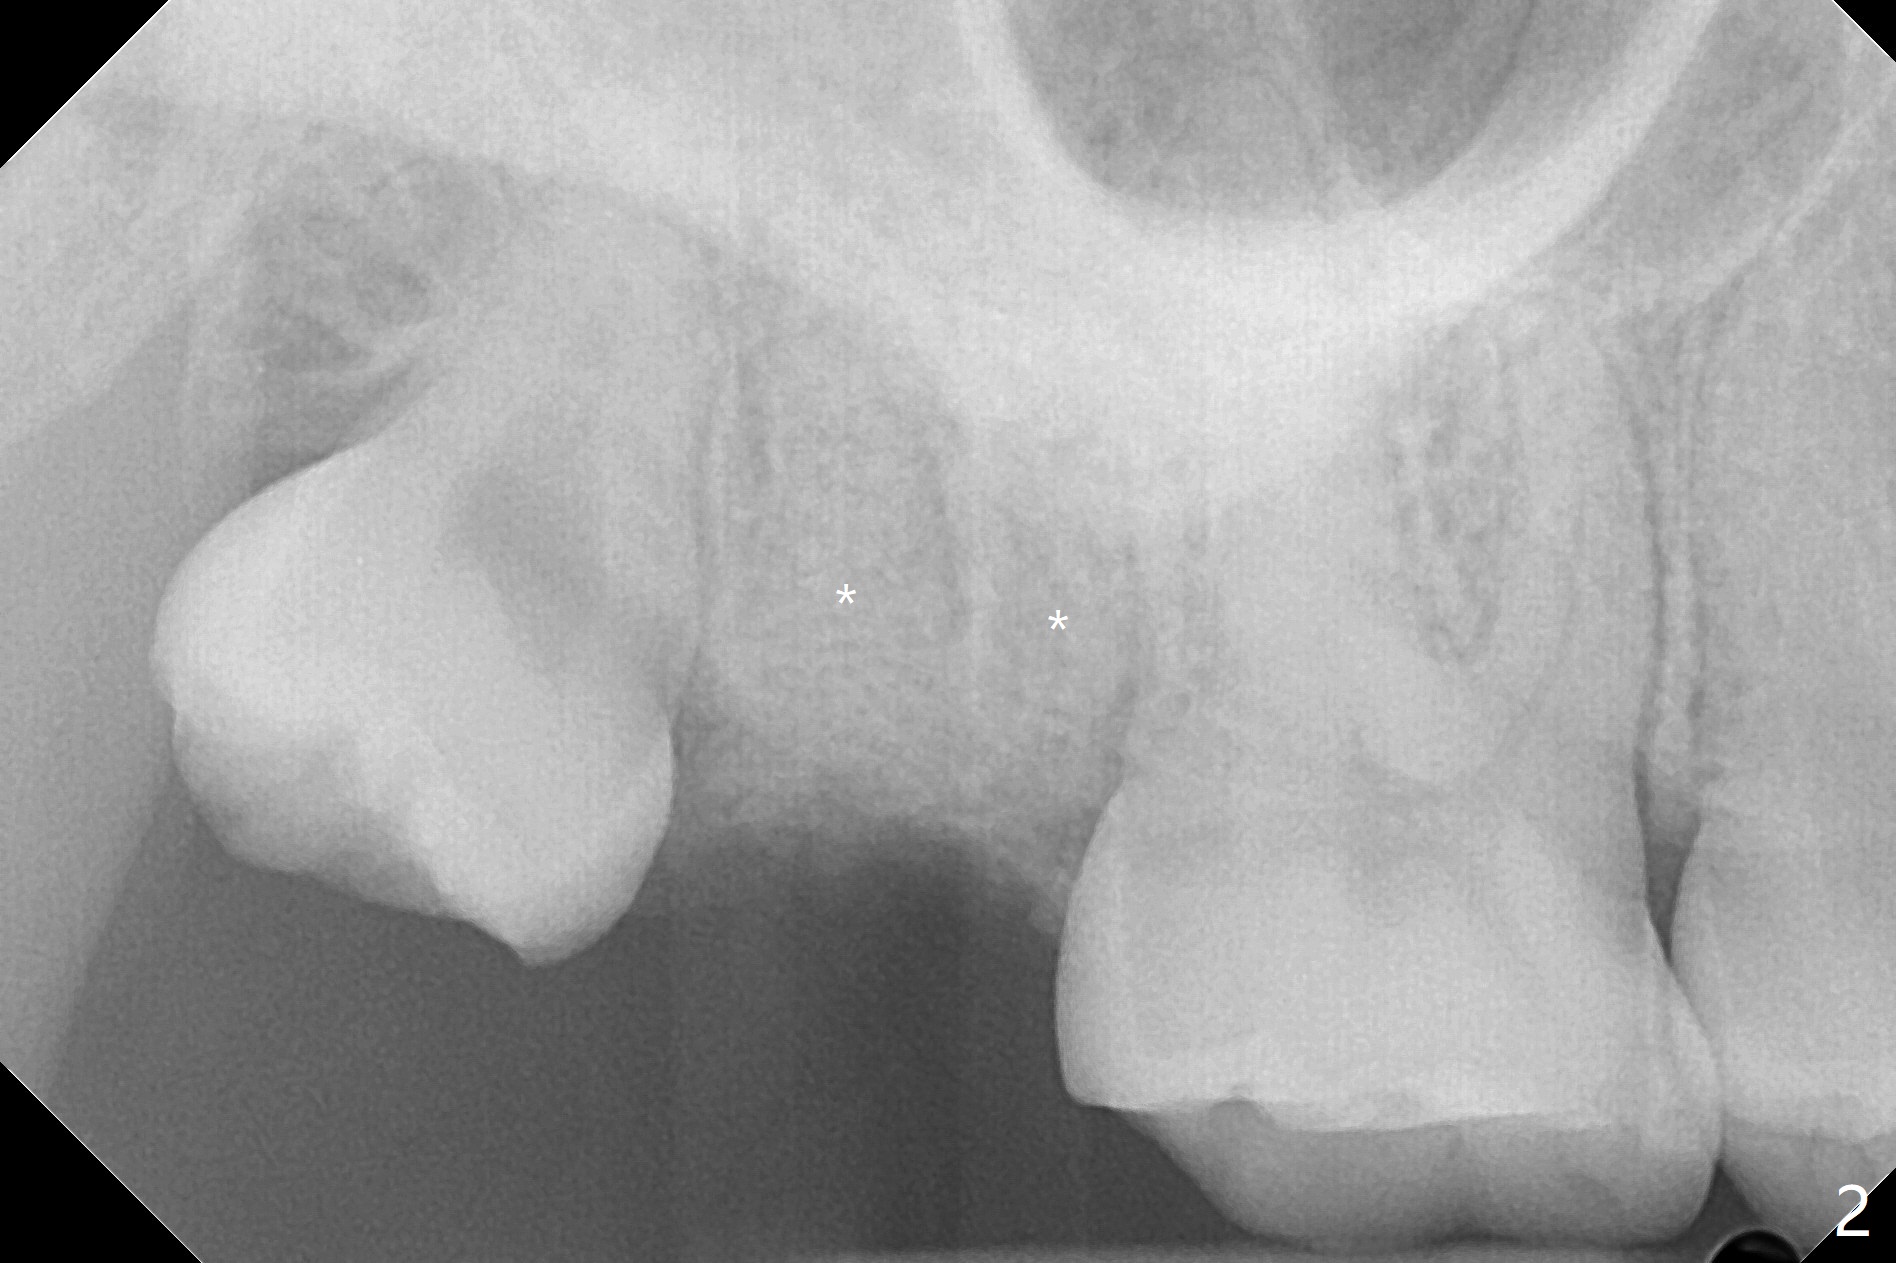

A 32-year-old nervous woman presents emergently with toothache at #2 with subgingival caries (Fig.1). She is unwilling to have #1 extracted. Vanilla graft and ß-TCP hydrated with GEM21S (Fig.2 *) are placed in the three sockets with distinct septa (good blood supply for regeneration). A 12x12 mm BioXclude is used to close the socket opening. After 4/0 PGA suture, periodontal glue is applied for retention of the suture and the membrane.